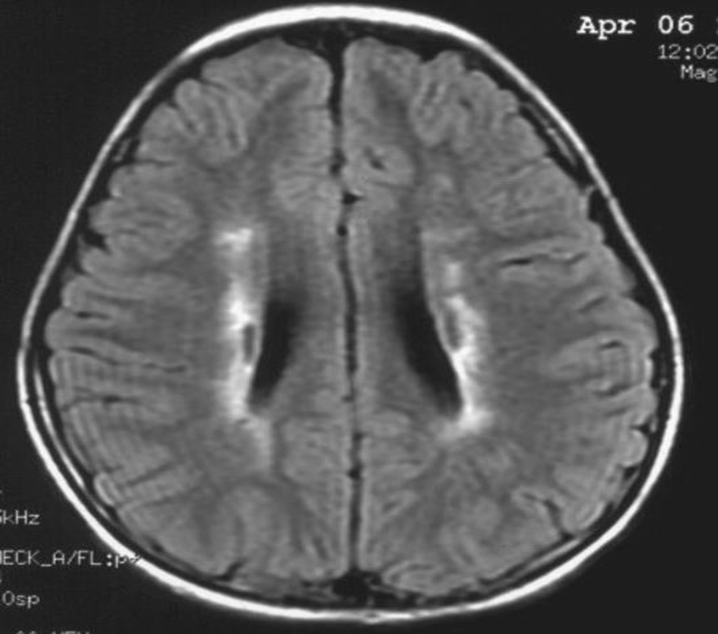

患者:林某某性別:男年齡:8 歲基本情況:出生后3個(gè)月臨床和頭部CT檢查診斷為腦癱。8年來(lái)病人曾在全國各地接受各種中西醫治療,病人入院時(shí)確診為痙攣性腦癱。治療時(shí)間:2005年7月接受干細胞移植手術(shù)。